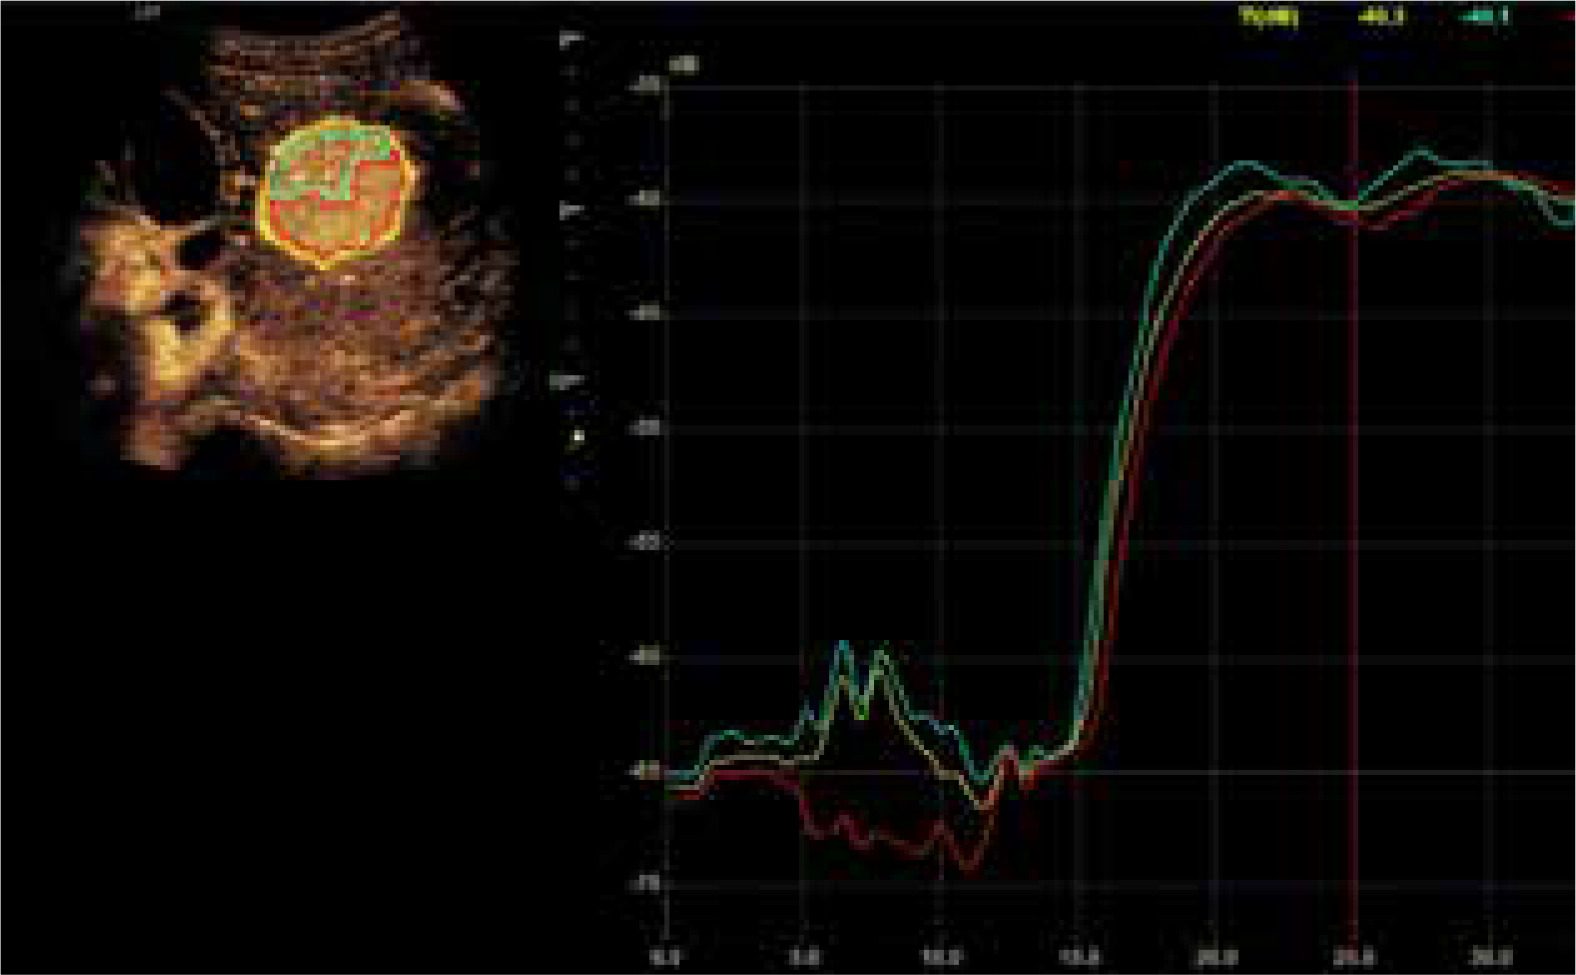

Fig. 3

Assessment of the degrees of enhancement in the post-contrast examination (CEUS). Areas of interest were placed within the lesion (depending on the size of the lesion and the uniformity of the enhancement – one or two areas – G). Another area was placed in the parenchyma of the liver – W, and in the lumen of a large vessel (most often vessels of the portal circulation – N). Enhancement curves were recorded in about 2-3 min in sequences of about 20-30 s. Values burdened with motor artifacts causing the dislocation of areas of interest were eliminated